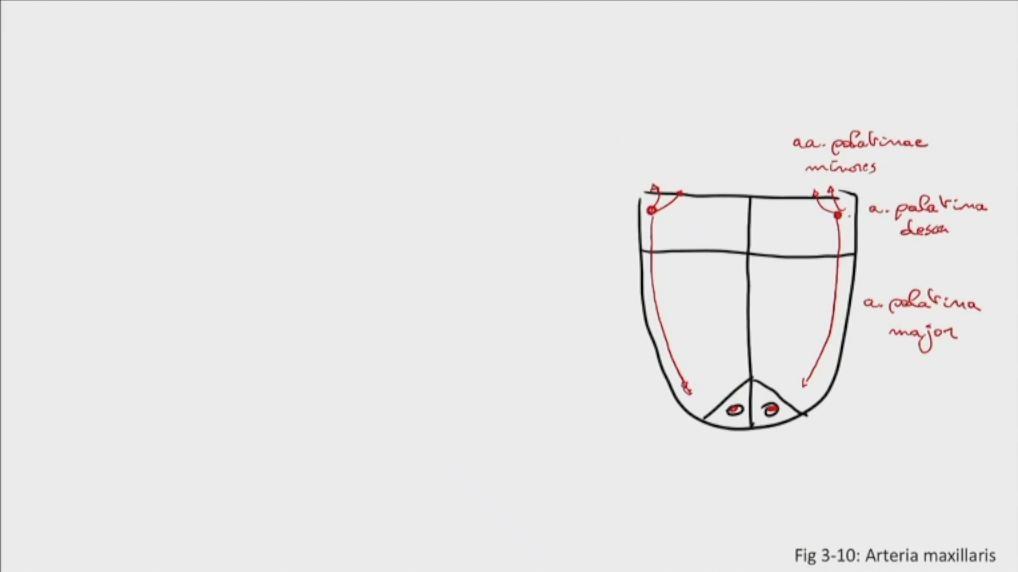

Fig 3.10c: a. maxillaris - sfenomaxillair deel - verhemelte

-

a palatina descendens

-

a palatina maior

aa palatinae minores

|

|